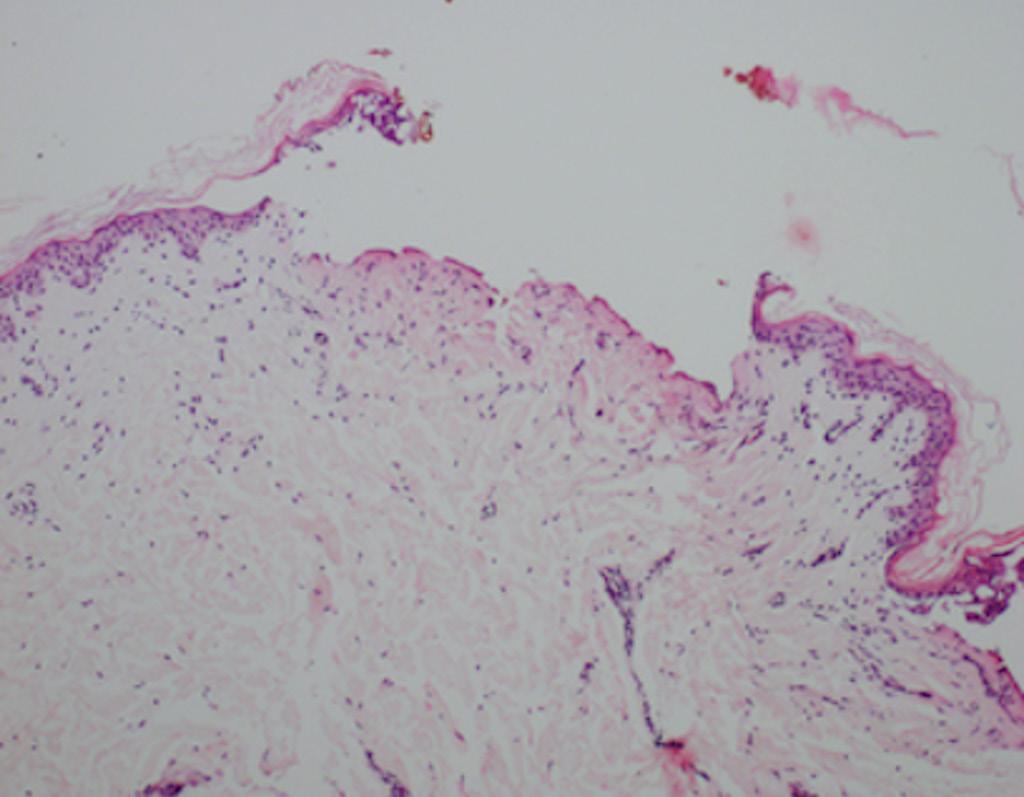

Histological comparison of the action of CO2 laser and plasma in abdominal skin

Ana Gabriella Bandeira Freire Andrade, Rossana Cantanhe de Farias de Vasconcelos, João Guilherme Finizola de Vasconcelos, Ana Mar ia Bertelli Antonio Gallotti, Caroline Costa de Mendonça